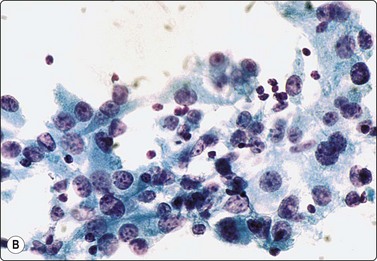

image image

Fig. 6.10 Hashimoto’s thyroiditis

Aggregates of oxyphil cells; background of blood and lymphocytes; note abundant cytoplasm, anisokaryosis and prominent nucleoli in A, more numerous lymphoid cells in B (A, MGG, HP; B, Pap, HP).

A bloody background with lymphoid cells, degenerative changes in follicular cells and infiltration of follicular cells by lymphoid cells are characteristic features of HT. Variable features include oxyphilic cells (Hurthle cells), plasma cells, epithelioid cell granulomas and multinucleated giant cells.

The ‘lymphocytic’ pattern of HT occurs in children and young adults with a shorter history of the disease and absent or low antibody titers.88 Smears are dominated by a mixed population of lymphoid cells including centroblasts, immunoblasts and dendritic reticulum cells from germinal centers characteristic of a reactive lymphoid proliferation (Fig. 6.12). Germinal center histiocytes have plentiful pale cytoplasm and oval or indented histiocytoid nuclei with granular chromatin. They are often clustered and associated with lymphoid cells, some of which lie within their cytoplasm. Histiocyte-lymphocyte rosettes or lympho-histiocytic clusters may be seen. Lymphoid : follicular cell ratios are often as high as 10 : 1 with epithelial cells so inconspicuous that smears resemble reactive lymphoid hyperplasia (Fig 6.12 A).

‘Classic’ or ‘florid’ HT occurs in older patients (usually women), who are more often hypothyroid and have raised TPO-Ab. The smear background shows lymphocytes with a variable number of plasma cells. There is prominent oxyphilic (Hurthle cell/Askanazy cell) change with single and syncytial aggregates of cells showing abundant, dense, finely granular, gray-blue cytoplasm (MGG), and well-defined cell borders. Nuclei are 2–4 times the size of normal follicular cell nuclei (Figs 6.10 and 6.11) and may show atypia and prominent nucleoli. Normal-appearing follicular cells may be present, showing features of hyperactivity. A characteristic feature is that of lymphocytes (and occasionally plasma cells) seeming to adhere to or infiltrate follicular cells, supporting the theory of direct epithelial damage by lymphocytes. Multinucleated giant cells and epithelioid cells can be seen in up to 40% of cases.87,93 Neutrophils and eosinophils may be seen adhering to or infiltrating follicular cells in early stages.42,93